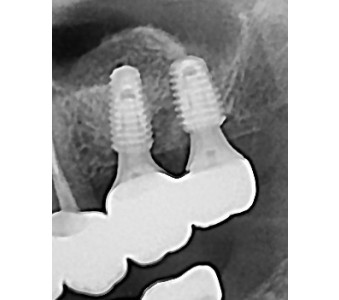

오스템 임플란트 프리미엄 BA 등급 사용

같은 오스템이라도 등급이 다릅니다. 더 빠른 골유착을 위해 프리미엄 등급을 사용합니다.

결과로 증명합니다.

국제모아치과의

실제 임상 증례